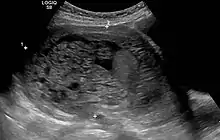

In rare cases a hydatidiform mole co-exists in the uterus with a normal, viable fetus. These cases are due to twinning. The uterus contains the products of two conceptions: one with an abnormal placenta and no viable fetus (the mole), and one with a normal placenta and a viable fetus. Under careful surveillance it is often possible for the woman to give birth to the normal child and to be cured of the mole.[9]